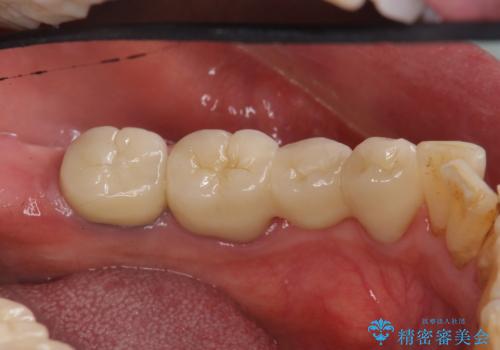

- 他院で右下小臼歯が保存不可能と言われ来院。当院の判断でも残念ながら抜歯となり、欠損部は抜歯後ブリッジにしました。右下奥2本が連結されていたため、そこは各々切り離した形で被せ物のやり替えも行っています。

- 約60万円 右下④5⑥:ジルコニアクラウンブリッジ 11万円×3 仮歯 1万円×3 根管治療費用別途費用は治療当時の料金となります

抜歯後3か月ほど仮歯で生活していただき、欠損部の歯肉の状態が安定してからブリッジを入れています。